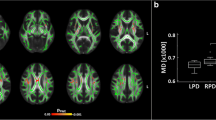

STN FA

Mean STN FA values were 0.36 ± 0.09 for the PD group and 0.43 ± 0.11 for the healthy control group (Fig. 3). No significant difference in STN FA was observed between the left and right sides for both groups (p = 0.50). Age, sex, side and normalized STN volume were considered as adjusting variables, but their effects were not statistically significant (p > 0.08). Only the effect of subject group was statistically significant. The model estimated difference in STN FA between the healthy control and PD groups was found to be 0.07 (95% confidence interval [0.02, 0.12], t = −2.76, df = 45, p < 0.008, regression coefficient = −0.07), indicating a 19% higher average FA in the control subjects compared with the PD group.

STN-FA differences between the two groups. Blue indicates data for the PD group. Orange indicates data for the healthy control group. FA = fractional anisotropy. EPD = early Parkinson’s disease group. STN = subthalamic nucleus. * = Statistical significance p < 0.05 from a linear mixed model effect. The 25th and 75th percentiles are represented by the lower and upper boundaries of each box with median values represented by the middle band within the box.

In the second statistical model, factors contributing STN FA in the PD group were examined. Adjusting factors of age, sex and side were not significant. The factor of MDS-UPDRS III score was also not significant (p = 0.10). The adjusting factor of STN volume was statistically significant (t = −2.67, df = 28 p = 0.01, regression coefficient = −0.002). An inverse association between normalized STN volume and STN FA was observed. Lateralized MDS-UPDRS III scores were used in a separate model but the results were not statistically significant (p = 0.41).